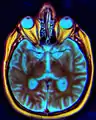

المخ من أسفل.